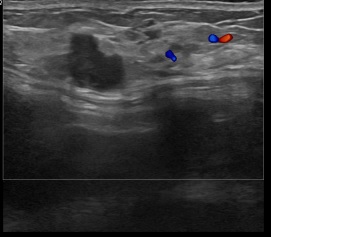

상기환자는 외부건진이상소견 만져지는 좌측유방멍울 조직검사위해 내원하신 40대 후반

여성분으로 의심스러운 좌측혹 조직검사 시행해 유방암 진단되었습니다.